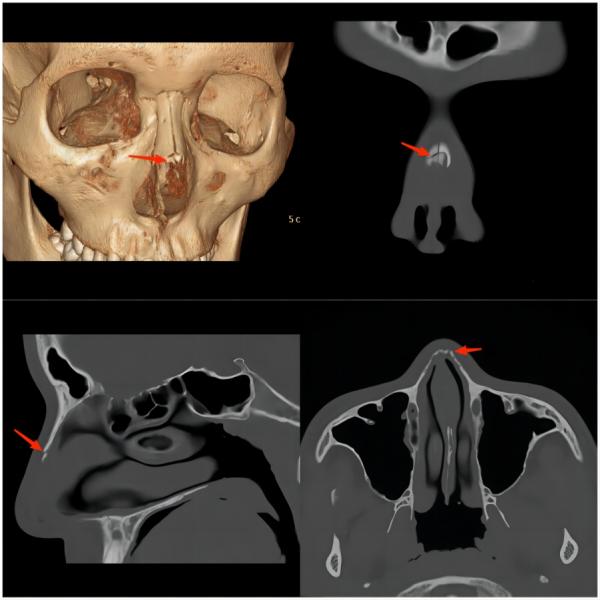

③ 颅面部损伤

运动损伤知识科普宣传内容,关于足球运动损伤调查问卷

(上图为鼻骨骨折)

(上图为颅骨骨折并颅内出血)

常见原因:多因球员在奋力争顶球时与对方球员的头或腿部相撞,或冲顶攻门时头撞到门柱而受伤,以颅面骨骨折及颅内出血多见。因此,常会看到两名球员为争抢头球时头部撞在一起倒地不起的画面。